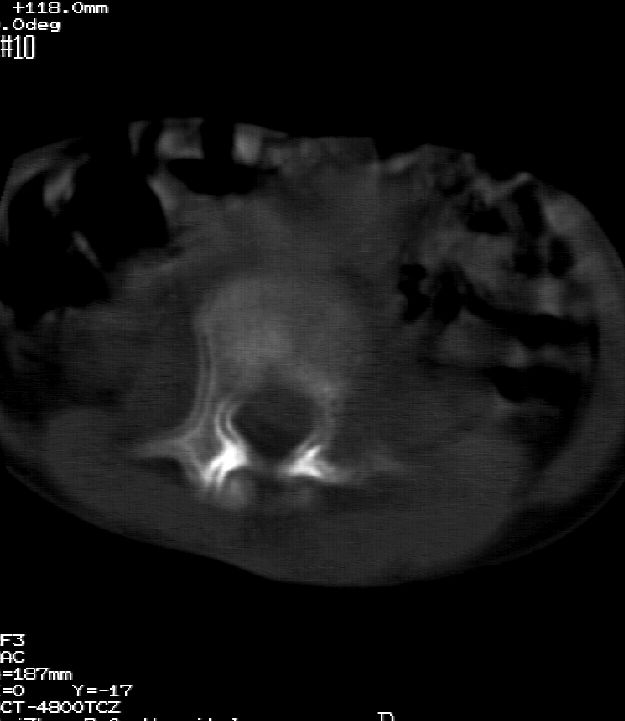

患儿女,11岁,因“腰痛,腰部活动受限10余天”入院。

10余天前,患儿无明诱因出现腰部疼痛,为持续性钝痛,以右侧为著,伴腰部活动受限,有发热,具体体温不详,无寒战、黄疸、盗汗、咳嗽,无尿频、尿急、肉眼血尿。

乍一看像是嗜酸性肉芽肿,但看到ct表现骨质破坏及软组织肿胀考虑结核可能性大,鉴别恶性肿瘤.

本例ct图像太不清楚了,而且不知道有没有传完,如果软组织病变只局限性于那几个层面的话多考虑嗜酸性肉芽肿,其次为其他肿瘤,结核椎旁软组织较广泛,在本例没有太典型表现,建议楼主(孩子父母吧)把所有的软组织窗图像(白色的那种)按顺序全部转上来.

考虑l3嗜酸性肉芽肿。